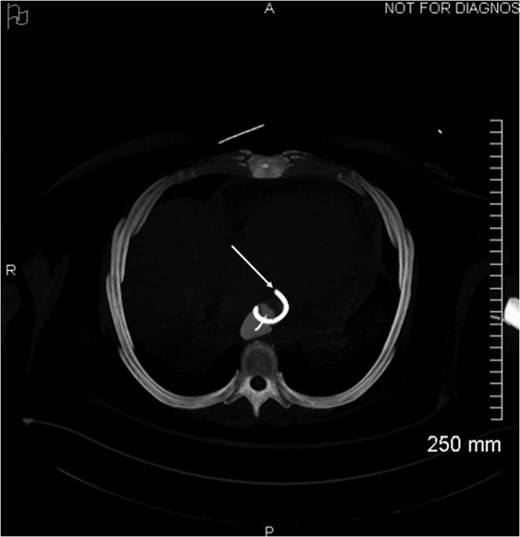

Proximal end of the double pigtail drain externalizes in the pericardium (arrow).

Axial view of opacification on CT showing the externalization of the drain in the pericardium (arrow).